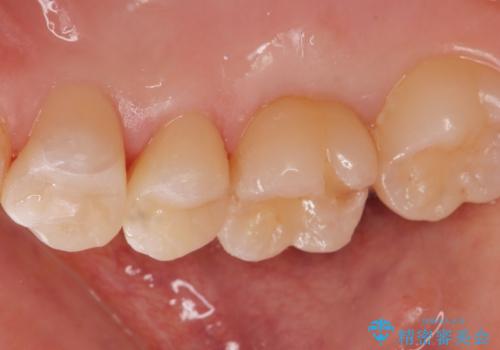

適合の良い詰め物が入りました。

セラミックは適合がよく虫歯の再発のリスクが低くなります。